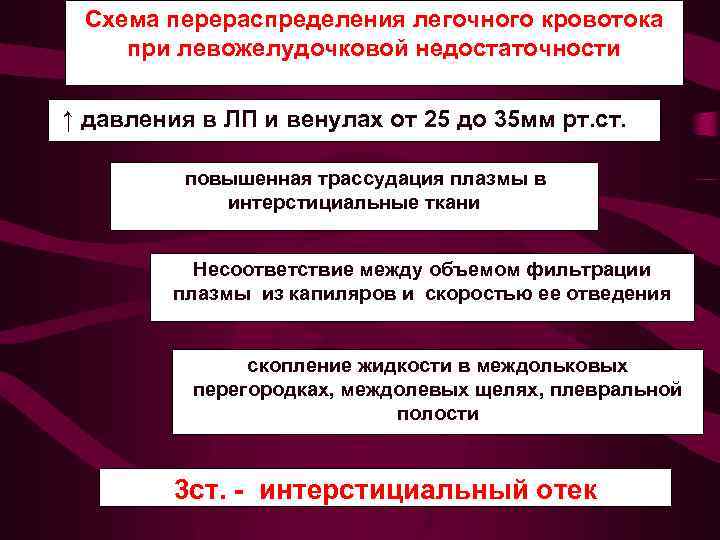

Схема перераспределения легочного кровотока при левожелудочковой недостаточности ↑ давления в ЛП и венулах от 25 до 35 мм рт. ст. повышенная трассудация плазмы в интерстициальные ткани Несоответствие между объемом фильтрации плазмы из капиляров и скоростью ее отведения скопление жидкости в междольковых перегородках, междолевых щелях, плевральной полости 3 ст. - интерстициальный отек

Схема перераспределения легочного кровотока при левожелудочковой недостаточности ↑ давления в ЛП и венулах от 25 до 35 мм рт. ст. повышенная трассудация плазмы в интерстициальные ткани Несоответствие между объемом фильтрации плазмы из капиляров и скоростью ее отведения скопление жидкости в междольковых перегородках, междолевых щелях, плевральной полости 3 ст. - интерстициальный отек

3 - интерстициальн ый отек легких Среднее давление в левом предсердии от 25 до 35 мм рт. ст. На фоне диффузного венозного застоя выявляются признаки нарушения лимфооттока из легких. Прозрачность легочных полей понижена. Легочный рисунок усилен, полиморфный, наблюдается ячеистая его деформация с нечеткостью контуров сосудов и бронхов. Выявляются линии Керли, Выпот в плевральную полость и междолевые щели, чаще справа.

3 - интерстициальн ый отек легких Среднее давление в левом предсердии от 25 до 35 мм рт. ст. На фоне диффузного венозного застоя выявляются признаки нарушения лимфооттока из легких. Прозрачность легочных полей понижена. Легочный рисунок усилен, полиморфный, наблюдается ячеистая его деформация с нечеткостью контуров сосудов и бронхов. Выявляются линии Керли, Выпот в плевральную полость и междолевые щели, чаще справа.